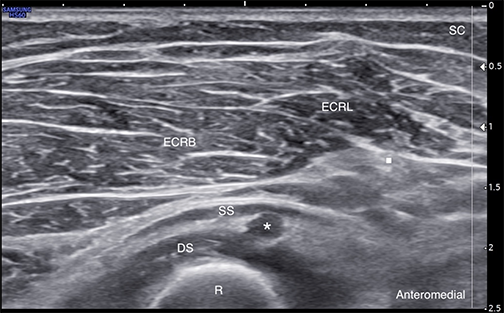

Labeled short-axis ultrasound image of the deep motor branch of the radial nerve at the arcade of Frohse, showing nerve enlargement, with loss of the normal honeycomb fascicular pattern and hypoechogenicity. * = Deep motor branch of the radial nerve ECRB = Extensor carpi radialis brevis muscle ECRL = Extensor carpi radialis longus muscle DS = Supinator muscle deep head SS = Supinator muscle superficial head R = Radius SC = Subcutaneous tissue